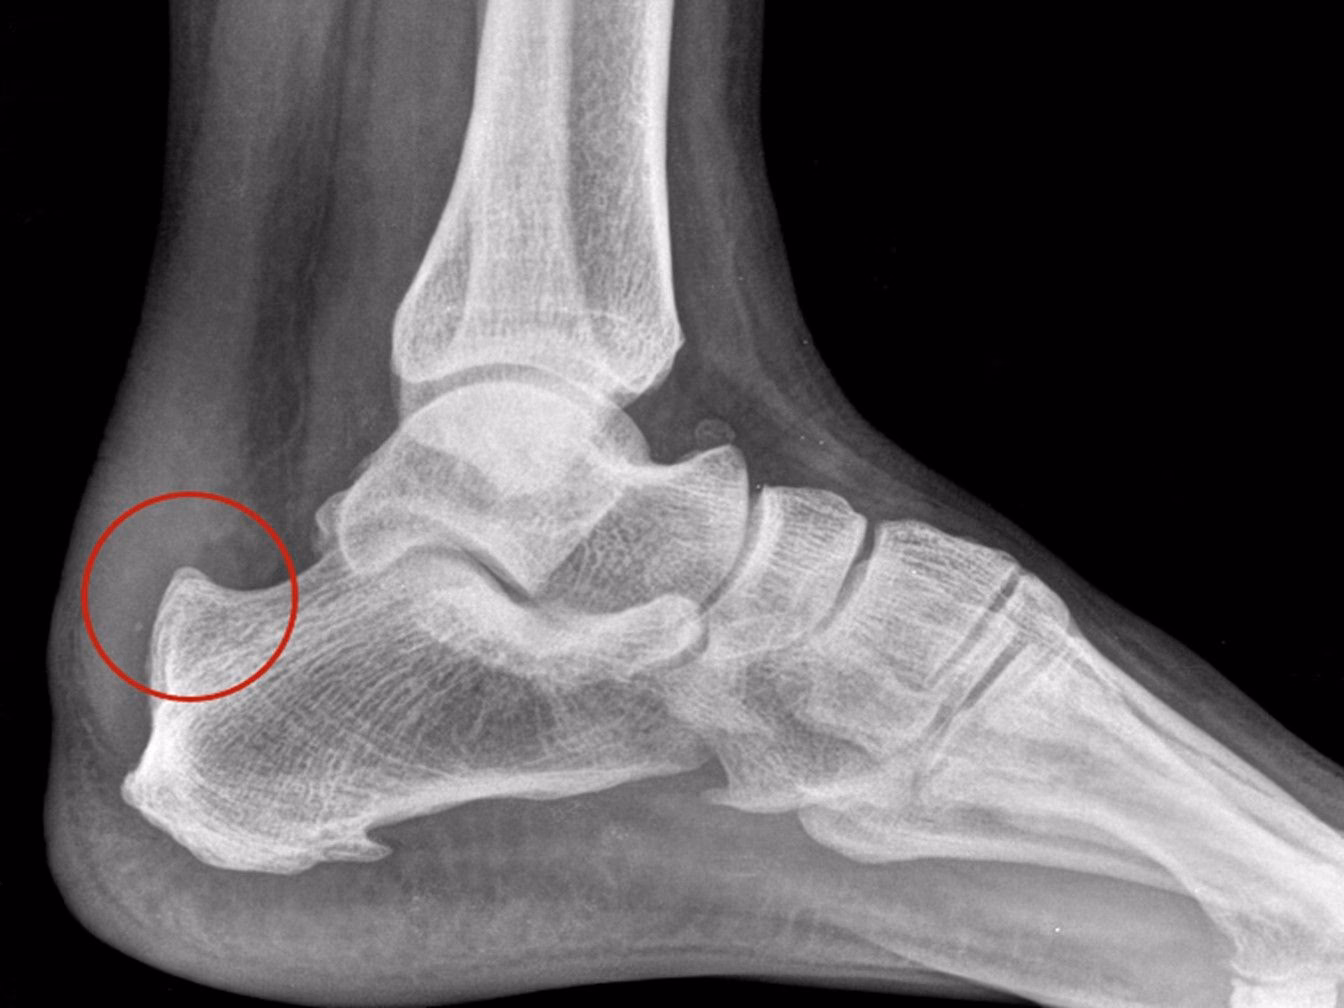

- Radiografía Lateral del Pie: Es la prueba inicial más útil. Permite visualizar claramente la exostosis o espolón en la parte posterosuperior del calcáneo. También puede mostrar signos de inflamación de la bursa calcánea y, en ocasiones, formación ósea heterotópica en la inserción del tendón de Aquiles. Se pueden utilizar mediciones radiográficas, como el ángulo de Fowler-Pilliphs, aunque su correlación con los síntomas no siempre es directa.